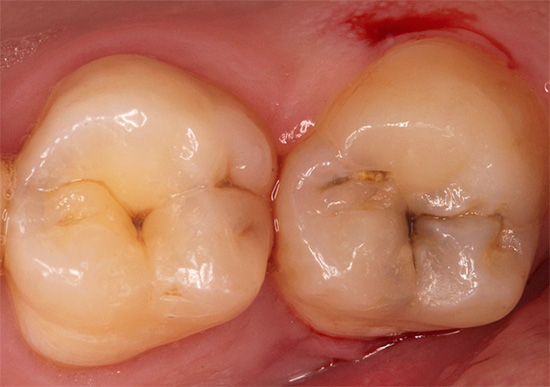

La diagnosi della carie delle ragadi in molti casi è abbastanza semplice, poiché le lesioni dello smalto sono chiaramente visibili ad occhio nudo. Ma a volte, specialmente nelle fessure profonde, risultano completamente invisibili e la sonda dentale non si ferma nemmeno in esse con questa diagnosi strumentale.

Le fessure stesse hanno un'ombra più scura rispetto al resto della superficie dello smalto dei denti. Ciò è dovuto al fatto che sono pieni di placca, placche dentali che non possono essere completamente rimosse con uno spazzolino da denti e che si trovano semplicemente in nicchie all'ombra dei tubercoli del dente. Tutto ciò spesso nasconde la carie delle fessure e rende difficile il rilevamento.